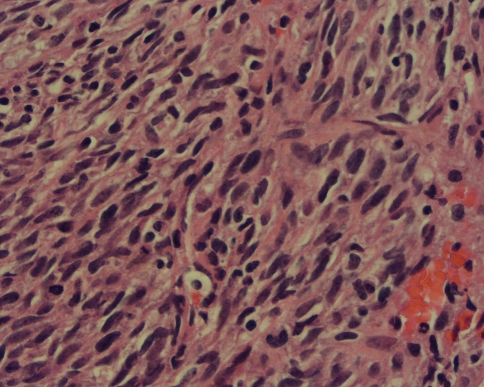

Fig. 6.

A high-power view shows atypical plump oval to spindle cells with moderate eosinophilic fibrillary cytoplasm. Isolated mononuclear small lymphocytes also are present (Stain, hematoxylin and eosin; magnification, ×40).

The tumor was comprised of plump atypical spindle and ovoid cells arranged in a fascicular or herringbone-type pattern (Fig. 5). The cells appeared immature with minimal to mild eosinophilic fibrillary cytoplasm. There was minimal pleomorphism and frequent mitoses (10–11 per 5 high power fields.) The mass also contained scattered amounts of chronic mononuclear inflammatory cells (Fig. 6). Focal areas of hemorrhage and necrosis also were identified. Immunohistochemical staining for CD34, CD31, Factor VIII, HHF-35, SMA, desmin, S-100, and keratin were all negative. CD99 was positive. Ki-67 (proliferative index) was approximately 20% to 30%. FISH analysis for FKHR on 13q14, SYT on 18q11.2, and EWSR on 22q12 were negative. Reverse-transcription polymerase chain reaction (RT-PCR) was positive for ETV6/NTRK3 t(12;15)(q13;q25) translocation.

Microscopically, congenital fibrosarcoma is a hypercellular, hyperchromatic, anaplastic spindle cells tumor arranged in a herringbone pattern, with frequent mitoses, necrosis, and hemorrhage [4]. Immunohistochemistry and cytogenetics often are needed, and show negative staining for SMA, S-100, desmin, CD31, and CD34 [19]. Congenital fibrosarcoma is characterized by a recurrent t(12;15)(p13;q25) rearrangement, producing the ETV6 (TEL):NTRK3 (neurotrophin-3 receptor) fusion protein identified by RT-PCR [20, 34] and not expressed by the adult-type fibrosarcoma [33].